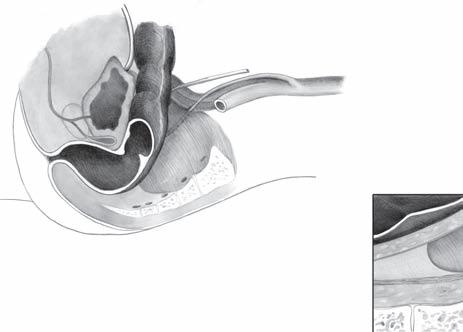

2.3 Chirurgická topografie malé pánve

Znalost topografických vztahů rekta k okolním orgánům v malé pánvi je předpokladem přesné preparace při operaci (obr. 2.6). Anatomické poměry v oblasti rekta, které je uloženo intraperitoneálně, jsou peroperačně většinou vizuálně přehledné. Po mobilizaci sigmoidea lze spolehlivě v retroperitoneu určit průběh levého močovodu, vasa ovarica či spermatica, průběh vasa iliaca communis a v oblasti promontoria plexus hypogastricus. Následná retroperitoneální mobilizace mezosigmoidea přes střední čáru (orientace podle aorty a páteře) umožní dostatečné ohraničení horního lymfatického pediklu, vasa rectalis superior. Dostatečná mobilizace mezosigmoidea usnadní před promontoriem ostře proniknout v avaskulární zóně do retrorektálního prostoru.

Extraperitoneálně je rektum ohraničeno viscerální rektální fascií, fascia propria, která jako tenká vrsta pokrývá mezorektum a přechází na přední stěnu rekta. Viscerální list tvoří důležitou bariéru pro diseminaci tumorů rekta. Retrorektálně na dolním rektu (na úrovni anorekta) fascia visceralis splývá s Waldeyerovou fascií. Jde o úroveň S4, kde se rektum zatáčí dopředu a Waldeyerova fascie rektum fixuje k sakru. Waldeyerova fascie, navazující na levator ani, presakrálně pokračuje jako parietální rektální fascie. Parietální list (parietální pelvická fascie, parietální list presakrální fascie) pokrývá povrch os sacrum, os coccygeum a svalů přilehlého dna

a. mesenterica inf.

ureter a. iliaca com.

ureter

fascia Denonvillieri

Obr. 2.6 Topografie malé pánve u muže

n. sympaticus

a. rectalis sup. S3

fascia presacralis

semenné váčky prostata

pánevního. V avaskulárním prostoru mezi viscerálním a parietálním listem presakrální fascie probíhají nervi hypogastrici, které lze vizuálně identifikovat při ostré preparaci (obr. 2.7). Jak bylo uvedeno výše, viscerální rektální fascie extraperitoneálně posterolaterálně ohraničuje mezorektum. Anatomicky je název „mezorektum“ nepřesný. V chirurgické literatuře se tento termín běžně používán pro tukovou tkáň obklopující jako polštář rektum, v které probíhají cévní a lymfatické svazky zásobující rektum, vasa rectalis superior a vasa rectalis media. Mezorektum začíná od promontoria jako pokračování mezosigmoidea a končí na Waldeyerově fascii, tedy na dně pánevním. Laterálně nacházíme v mezorektu pevnější vazivové struktury, obkružující vlákna autonomních nervů, která přicházejí k rektu z pelvického plexu. Tyto struktury jsou známy jako laterální ligamenta či paraprokcia a spojují stěnu malé pánve s mezorektem. Při totální excizi mezorekta je doporučována resekce laterálních ligament s následnou ligaturou tak, aby byla zachována integrita mezorekta a byly ligovány jen nervové pleteně inervující rektum. Podobně i ostrá disekce v avaskulárním prostoru mezi parietálním a viscerálním listem presakrální fascie zachová integritu mezorekta a uchrání autonomní nervové svazky. Vpředu je fascia visceralis recti (fascia propria) tenčí než vzadu a splývá s přední stěnou rekta. Rektum je ale od pohlavních orgánů odděleno denonvillierskou fascií, která je z hlediska embryologie reziduem dvouvrstevného slepého vaku peritonea (obr. 2.8). Denonvilliers popsal prostatoperitoneální fascii u mužů, ekvivalentní vrstvu lze však najít i u žen – fascia rectovaginalis. Vzhleprostata

močový měchýř ureter a. mesenterica inf.

rektum semenné váčky S3

stěna rekta mezorektum fascia visceralis fascia parietalis

os sacrum

Obr. 2.7 Zadní disekce mezorekta

dem k tomu, že vývojově jde o zbytek slepého peritoneálního výběžku, lze sledovat u dennonvillierské fascie jednu vrstvu adherující k semenným váčkům a prostatě a druhou vrstvu naléhající těsně na přední plochu rekta.

Obr. 2.8 Přední disekce u muže mezorekta